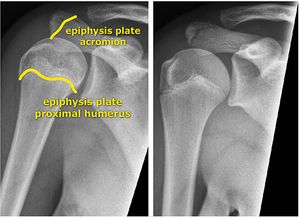

어깨는 쇄골, 견갑골, 상완골로 구성되어 있다.[54] 쇄골과 견봉은 어깨 너비의 대부분을 차지하며, 성장판을 통해 성장한다. 사람마다 어깨는 다르지만 대부분 비대칭이다. 보통 오른손잡이는 오른쪽 어깨 길이(오른쪽 쇄골-견봉)가 왼쪽보다 길고, 왼손잡이는 왼쪽 어깨 길이(쇄골-견봉 길이)가 오른쪽보다 길다. 대개 0.5cm 내외로 차이가 난다.양쪽 쇄골 길이가 2cm 이상 차이가 나면 기능상 문제가 있을 수 있으므로 병원에 방문해야 한다. 하지만 쇄골 성장판이 심하게 다치거나 골절되어 조기 폐쇄된 것이 아니면 2cm 정도 차이 나는 경우는 드물다. 쇄골은 0.1cm 자라는 데 오랜 시간이 걸리므로, 2cm 차이는 최소 6년 전에 쇄골에 부상을 입은 것이다. 따라서 6~7년 전 성장기에 쇄골 골절이나 부상을 입었다면 양쪽 쇄골 길이를 재보고 2cm 이상 차이 나면 병원에 가야 한다.

쇄골은 어깨 너비의 약 83.4%를 차지하며, 만 24~25세까지 성장하는 성장판을 가지고 있다.[54] 쇄골 양쪽 끝에 성장판이 있으며, 이 성장판은 인간의 성장판 중 길이와 부피 성장을 가장 오래하고 가장 늦게 닫힌다. 쇄골 성장은 평균 만 24~25세, 최대 30세까지 진행된다.

견봉은 쇄골의 끝부분부터 위팔을 만져보면 있는 뼈까지이다. 견봉 성장판은 만 18~22세 내외에 닫힌다.[55] 쇄골에 비하면 일찍 닫히는 편이지만, 전체적인 평균 성장판 폐쇄 시기로 보면 늦게 닫히는 편에 속한다. 견봉 길이의 평균은 남성 cm 기준 1.54cm이다.[56]